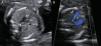

El diagnóstico ecográfico prenatal del AAD se realiza mediante un corte transversal del tórax fetal a nivel mediastínico, cuando el arco aórtico se sitúa a la derecha de la tráquea4 (fig. 2).

Imagen ecográfica del arco aórtico en el corte axial tres-vasos-tráquea. A) Arco aórtico izquierdo normal (20 semanas de gestación). B) Arco aórtico derecho con Doppler color (arco aórtico derecho); se visualiza el trayecto anómalo del arco aórtico a la derecha de la tráquea (20 semanas de gestación).

Ao: aorta; AP: arteria pulmonar; T: tráquea; VCS: vena cava superior.